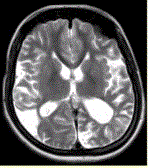

问题 女性,22岁。癫痫发作及智力异常。MRI显示见下图。 该病的诊断为

选项 A.海绵状血管瘤 B.发育性静脉畸形 C.AVM D.毛细血管扩张症 E.动脉瘤 F.硬脑膜动静脉漏 G.moyamoya

答案 G